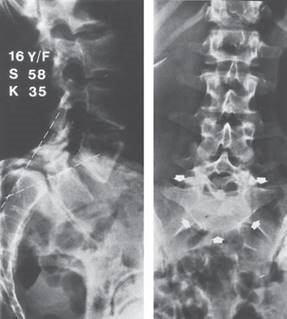

๐ŸŽ“ Viva 70

Illustration 19 for Ace FRCS Orthopaedics: Oxford University Press Adult Pathology Viva

๐Ÿ” Click to enlarge

Clinical Radiograph / Orthopedic Image

A B

Reproduced from C. Bulstrode et al., Oxford Textbook of Trauma and Orthopaedics second edition, 2011, fi gure 3.17.6, p. 249, with permission from Oxford University Press.

What do you understand by the term โ€˜isthmic spondylolithesisโ€™?

What are the other recognized causes of spondylolithesis?

How would you grade spondylolithesis and what radiographic indices maybe used to predict progression?

How do degenerative litheses differ from spondylolysis when considering neural involvement?

Spondylolithesis is an anterior sagittal plane translation of a vertebra upon the adjacent caudal level. Isthmic spondylolitheses are secondary to defects in the pars interarticularis at that level. It is most commonly seen at the lumbosacral junction with defects in L5. The spondylolysis is considered to be secondary to mechanical factors leading to a stress fracture of the pars, often in sports delivering impact forces to the hyperlordosed lumbar spine in a genetically predisposed population.

T he other forms of spodylolithesis as described by Wiltse and Newman are Type I dysplastic, (Type II isthmic), Type III degenerative, Type IV traumatic, Type V pathologic, and Type VI iatrogenic.

How would you grade spondylolithesis and what radiographic indices maybe use to predict progression?

M eyerding graded lateral radiographs Iโ€“IV sequentially for each 25% slippage with spondyloptosis being a complete slip without endplate to endplate contact. Standing lateral radiographs can be assessed for pelvic incidence, sacral slope, pelvic tilt, and lumbosacral angle which have all been quoted as predictors of progression. Eff ectively all these parameters look at lumbosacral shear.

How do degenerative litheses diff er from spondylolysis when considering neural involvement?

T he striking diff erence is when the posterior elements are considered. In isthmic spondylolithesis the lamina of the aff ected level remains posteriorly placed and thus central and lateral recess stenosis are seen much less commonly than foraminal stenosis. In these cases a combination of degenerate disc and residual (cephalad pars interarticularis) and reduced foraminal height below the displace pedicle results in radiculopathy. This contrasts with degenerative slips where all three forms of neural encroachment can be seen resulting in a broader spectrum of symptoms.